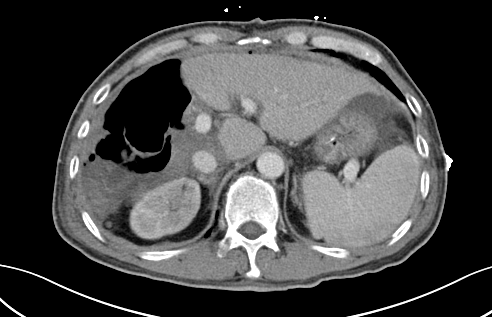

第一次手術(shù)后

經(jīng)過20天左右的“養(yǎng)肝”,經(jīng)CT復(fù)查顯示,患者的左側(cè)肝臟體積已增長至42.8%,這時候,也就達(dá)到了我們說的“養(yǎng)大好肝、再切病肝”,因?yàn)榇藭r好肝已經(jīng)足以維持患者身體的運(yùn)轉(zhuǎn)需要。